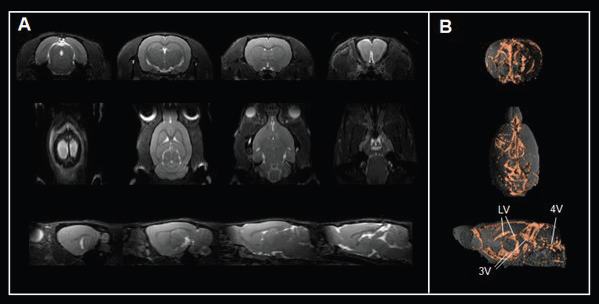

For instance, true fast imaging with steady-state precession (TrueFISP) sequence contrasts cerebrospinal fluid spaces (Fig. 5A) and 3D renderings (Fig. 5B), allowing the assessment of ventricle anatomy and morphology, a critical area for cerebrospinal fluid production and transport.

Disrupted ventricles are seen in numerous congenital neurological conditions and in response to neuronal injury or degeneration. Contrast-enhanced, flow and diffusion MRI approaches facilitate the monitoring of interstitial and cerebrospinal fluid flow through various extracellular compartments in the brain and spinal cord.

A number of neurological conditions exhibit changes in the magnitude and direction of cerebrospinal fluid flow, which are linked to impaired waste removal, accumulation of metabolites (e.g., lactate, ß-amyloid), and trafficking of immune cells. Assessing neuro fluid flow patterns with MRI can aid the assessment of different therapies to see whether they can restore normal fluid passage.

Figure 5. Assessing brain ventricles. A) Axial, coronal, and sagittal T2-weighted TrueFISP images and B) corresponding renderings reveal the cerebrospinal fluid spaces in the rat brain. Rat brain data was acquired with a BioSpec Maxwell 94/17 using a volume coil for transmission and a phased-array coil for reception. Tissues were segmented and rendered using PMOD. LV = lateral ventricle; 3V = third ventricle; 4V = forth ventricle. Image Credit: Bruker BioSpin Group